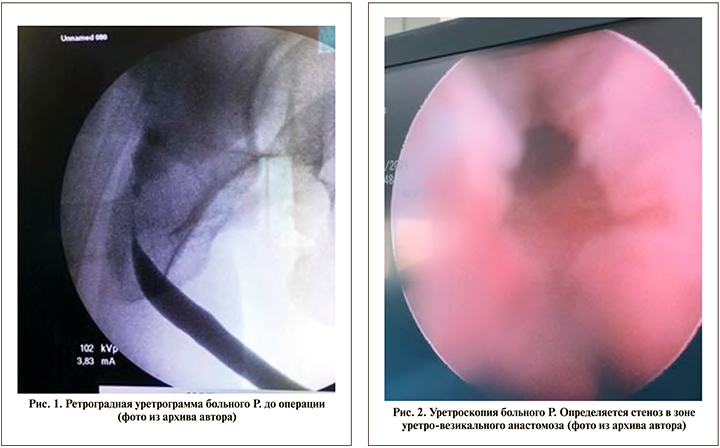

При обследовании пациент предъявляет жалобы на резко замедленное и ослабленное мочеиспускание. При лабораторном обследовании анализ мочи без патологических изменений, ПСА – 0,001 нг/мл. По данным урофлоуметрии, максимальная скорость потока мочи (Qmax) – 3,2 мл/с при объеме 150 мл и объеме остаточной мочи (Vres) 120 мл. При ретроградной уретрографии определяется непротяженный стеноз уретровезикального анастомоза (рис. 1).

При оптической ревизии мочеиспускательного канала определяется стеноз уретровезикального анастомоза до 4 Ch (рис. 2).